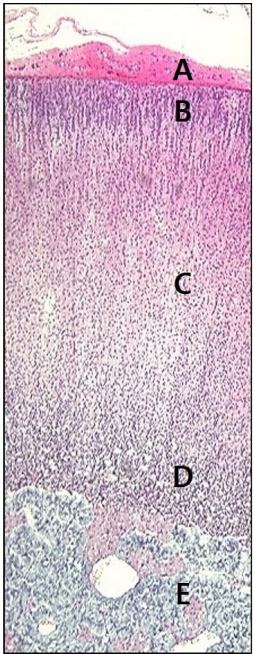

35세 남자가 두통, 두근거림과 함께 땀이 많이 난다며 병원에 왔다. 혈압 160/100 mmHg이다. 컴퓨터단층촬영 사진에서 오른쪽 부신에 덩이가 관찰된다. 혈액 카테콜아민 검사 결과는 다음과 같다. 그림에서 증상과 관련 있는 세포가 위치하는 곳은?

• A: capsule

• B: zona glomerulosa (mineralocorticoid 생성 – 예: aldosterone)

• C: zona fasciculata (glucocorticoid 생성 – 예: cortisol)

• D: zona reticularis (androgen 생성 – 예: DHEA)